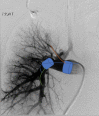

Bronchopulmonary arterial fistula consists of an abnormal connection between the bronchus and the vascular tree and is a rare but serious complication associated with a variety of lung interventions. We present a case of a 61-year-old female with a history of metastatic breast cancer treated with lumpectomy and radiation 20 years prior, who was found to have a fistula between the right pulmonary artery and the right mainstem bronchus. Our patient was treated endovascularly with coil embolization in the setting of massive hemoptysis flooding the trachea, which was successful in controlling the acute bleed, although care was withdrawn in the following days following a discussion with the family given the presence of advanced metastatic disease. This case illustrates the use of endovascular techniques to treat an actively bleeding bronchopulmonary arterial fistulae, including a review of the existing literature regarding the optimal endovascular management strategy. Although our patient did not achieve the best outcome, endovascular intervention with stent-placement or embolization can serve to temporarily halt blood flow through the fistula, stabilizing the patient and allowing for more radical therapy after improvement.